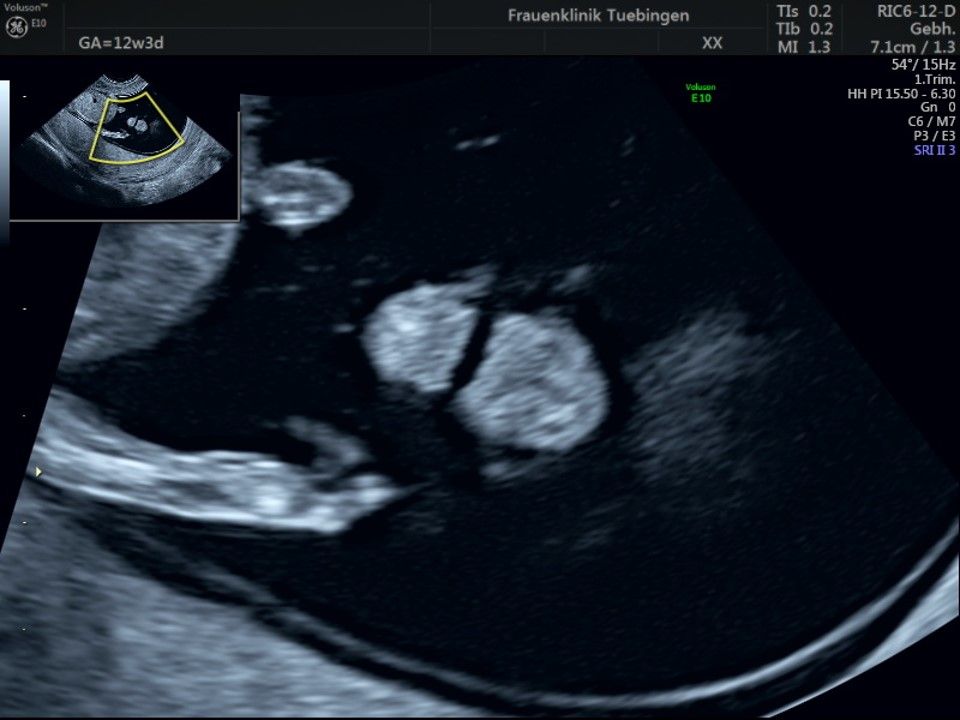

Herz